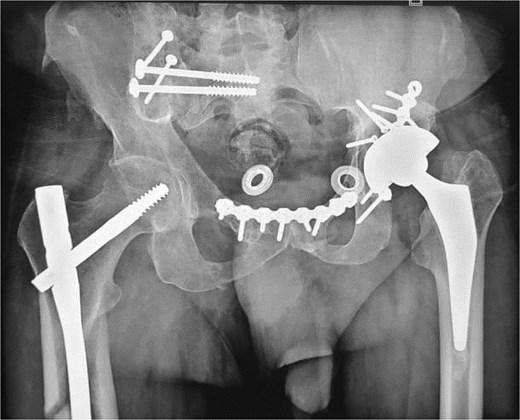

At the 10-month follow-up, the patient showed signs of left hip osteoarthritis with functional deterioration, for which a total ceramic-on-ceramic hip arthroplasty was performed, using a screw-fixed structural graft at the acetabulum (Fig. 3). At the final follow-up, 36 months postoperatively, the patient was walking unaided with the use of an anti-equinus splint on the left foot. The HHS was 85 and Majeed score was 86 [6, 7]. X-rays showed complete bone healing of all fractures and the acetabular graft. It should be noted that, during follow-up, the patient had a right femoral fracture that was successfully treated with a gamma nail (Fig. 4). Written informed consent were obtained from the patient.